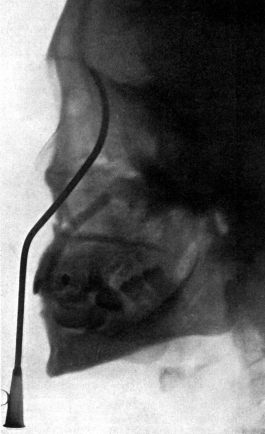

| 267. | Skiagram showing an Angular Tracheotomy Tube in the Trachea | 518 |

| 333. | Catheterizing the Frontal Sinus | 639 |

| 334. | Radiograph to show the Value of the Röntgen Rays | 639 |

| 335. | Radiograph showing Canula in the Frontal Sinus | 639 |